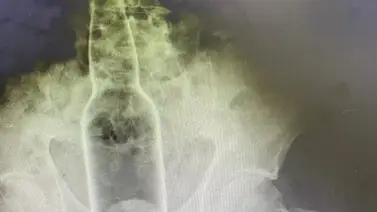

Intervienen a un hombre en Irán de urgencia luego de llegar a un hospital con fuerte dolor abdominal a causa de estreñimiento porque tenía una botella en el recto.

Los especialistas a través de una tomografía computarizada se percataron de la botella de agua dentro que medía 19 centímetros.

Tras esto, lo llevaron inmediatamente a cirugía para extraerle la botella. Afortunadamente el hombre no tuvo mayor complicación durante la extracción.